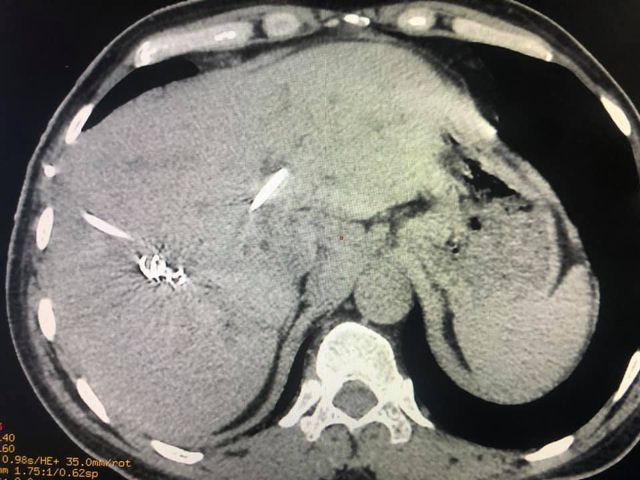

65 years of man type 3A hilar cholangiocarcinoma (complex hepatobiliary malignancy) with deep jaundice

SIX STEPS TO SUCCESS IN A ROLLER COASTER COVID CHALLENGE

- STEP 1: Left PTBD (to bring down jaundice)

- STEP 2: portal vein embolisation to allow growth of the small remnant left liver

- STEP 3: Right sided anterior and posterior PTBD to control persistent fever after initial intervention.

- STEP 4: admitted for surgery COVID positive CT CO-RADs 5 managed medically

- STEP 5: after 3 weeks waiting and repeat COVID PCR negative (couldn’t wait longer for risk of catheter dislodgement while waiting) underwent an Extended Rt hepatectomy with caudate lobectomy bile duct excision Left hepaticojejunostomy

- STEP 6: despite all the trials& tribulations and 7 hr surgery patient had a smooth recovery discharged by D6. An extremely satisfying result in a very difficult malignancy and a super motivated patient.